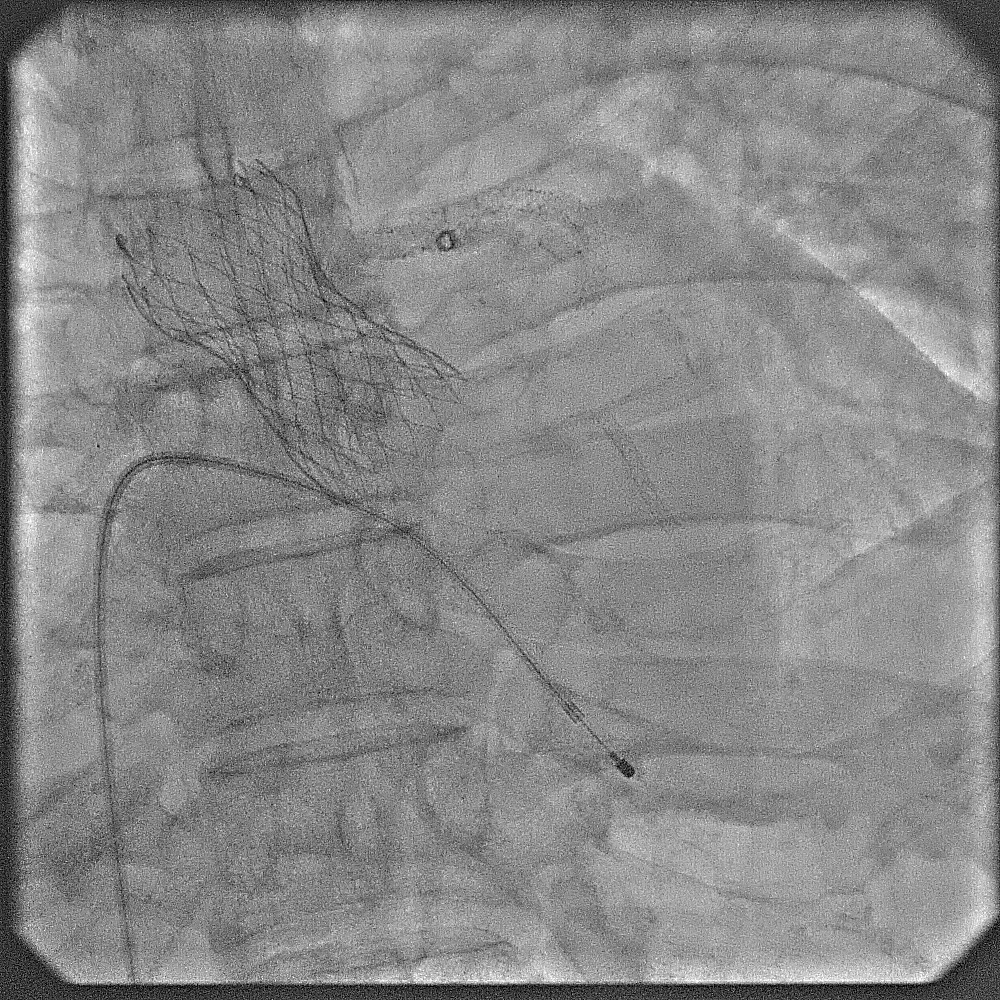

The case was referred to cardiac surgeon. Due to extensive calcification of the aorta, surgery was deemed highly challenging. With surgery declined, a staged procedure of PCI and transcatheter aortic valve replacement (TAVR) was planned. Throughout, contrast use was minimized to reduce renal injury.First Procedure: Initial PCI targeted the left coronary system. Pre-dilation was performed at left main ostium, followed by at the most obstructive lesion in the LCx to reduce the risk of ischemia in subsequent interventions. The mid-LAD was treated with a drug-eluting balloon (DEB), followed by the LCx with DEB. Finally, the left main ostium was stented with a drug-eluting stent (DES), achieving a favourable outcome. Total contrast volume used was 28 mL.Second Procedure: The next day, PCI was performed on the RCA. Despite the challenging ostial lesion, positioning of the guiding catheter (AL1) was successful. Balloon pre-dilation and placement of two DESs in the proximal RCA achieved satisfactory result. Total contrast used was 31 mL. The patient experienced significant relief from angina following these interventions.One Month Later: TAVR was performed using an Evolut Pro+. Due to severe iliofemoral and aortic calcifications, device delivery was challenging. TAVR was ultimately succesful; peak aortic valve gradient was decreased from 50 mmHg to no residual gradient.